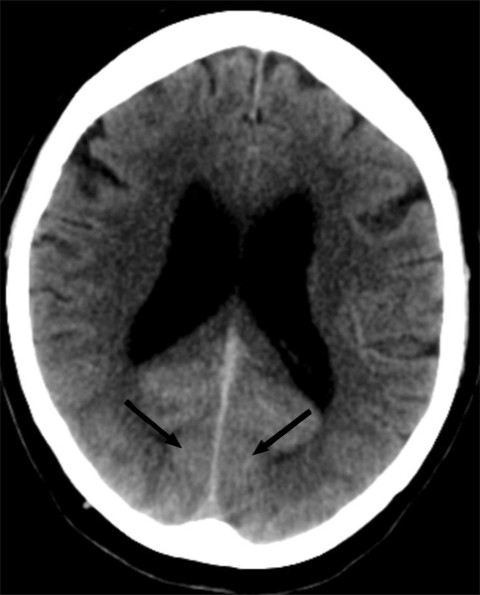

MR caput (T1- og T2-vektede sekvenser, FLAIR-sekvenser og diffusjon med ADC-verdier (apparent diffusion coefficient)) utført rett etter CT-undersøkelsen viste som tidligere uspesifikke T2- høysignal lesjoner, men ingen nytilkomne forandringer (figur 2). Det var ingen diffusjonsrestriksjon, som er forventet ved ferskt hjerneinfarkt (3).

På pasientens CT-bilder var det retensjon av kontrast i synsbarken på begge sider. CT-bildene var gjort uten kontrast, så den synlige kontrasten måtte være fra konvensjonell cerebral angiografi gjort to timer tidligere. CT-angiografi viste åpne kar. På MR var det ingen nytilkomne signalforandringer. De kliniske symptomene sammen med bildefunnene passet dermed ikke med cerebral iskemi på bakgrunn av tromboembolisme eller karspasmer.

Dette er en eksklusjonsdiagnose. MR caput og eventuelt CT caput med CT-angiografi er indisert for å utelukke blødning eller iskemisk årsak til synsaffeksjon. MR kan være negativ eller vise høysignal på T2- og FLAIR-signaler som ved vasogent ødem. CT kan vise normale funn eller kontrastoppladning oksipitalt. CT-angiografi fremstiller åpne kar uten spasmer.